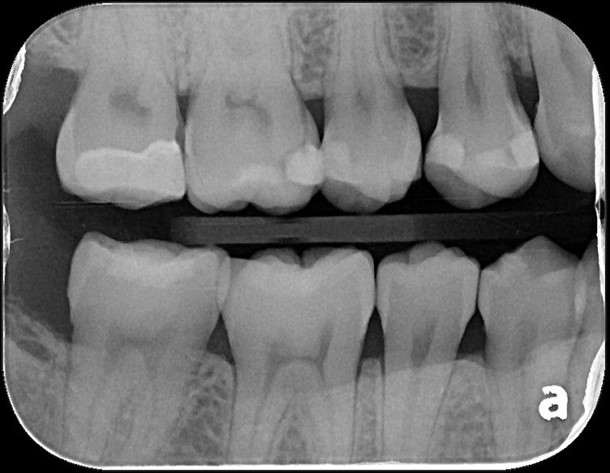

X光可見大臼齒內有蛀洞

治療後,X光密合度良好